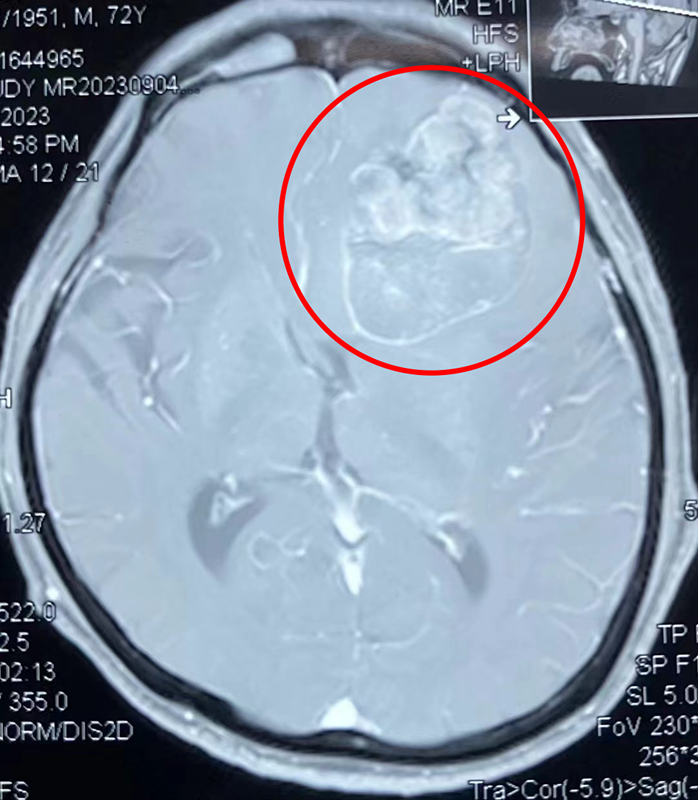

半年前,72岁的覃爷爷突然变得懒言少语,喜卧床,对常识问题不能回答;为求诊治,覃爷爷的家属带着他来到了广西科技大学第一附属医院门诊就诊,初步检查后以“颅内占位性病变”收住我科。入院后进一步完善影相关检查,高度怀疑患者系“颅内黑色素瘤(转移瘤)”,由于肿瘤侵犯大脑功能区,患者出现头痛、失语、反应力、记忆力明显减退、性格行为改变等临床表现。

颅内黑色素瘤,是一种较为少见的颅内恶性肿瘤。临床病程进展迅速,恶性程度较高。覃爷爷的肿瘤在右侧额叶区,属于脑功能区。功能区脑肿瘤的切除一直是神经外科医生面临的难题,保守切除肿瘤极易复发,患者预后不佳,扩大切除不仅症状、体征得不到改善,甚至还可能危及生命。因此,术中准确区分正常与异常组织结构至关重要。在四级手术前多学科会诊讨论会上,神经外科主任李松年提出在术中使用荧光显影辅助技术,达到最大程度、安全可靠的肿瘤全切除目的。经过周密的术前准备,在李松年主任医师指导下,由池超超副主任医师主刀,周元鼓副主任医师配合,在荧光显影技术辅助下,为患者实施开颅右侧额叶深部肿瘤切除术。

患者手术前后头颅核磁共振